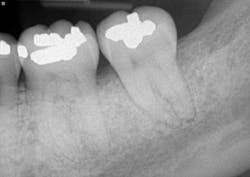

A clinical periodontal and radiographic assessment is completed. Although there is moderate bone loss in all four quadrants, his periodontal status is stable with the exceptions of Nos. 18 and 31 distal (figures 1 and 2). Both areas reveal direct distal probing depths of at least 10 mm and radiographic infrabony distal defects.

Figure 2: No. 31

In this case, No. 18 was treated nonsurgically with Visual-SRP using a dental endoscope. The root surface was debrided using a piezoelectric scaler with left- and right-angled periodontal tips. No other adjunctive therapies were utilized for this nonsurgical treatment. On the opposite quadrant, No. 31 was treated with traditional periodontal pocket reduction surgery and bone regenerative materials. The materials used included an allograft and enamel matrix proteins.

The patient returned after two weeks for a postoperative check of No. 31 and had a maintenance visit at three months post-op. At the three-month mark, the Visual-SRP area was evaluated for results. The pocket depth had resolved to 4 mm without signs of inflammation. A periapical radiograph of the area suggested bone remineralization in the site of No. 18 distal (figure 3). No. 31 was required to heal for six months and was not assessed until that time. At the six-month mark, the patient returned for another maintenance visit. The surgical area was measured, and the pocket depth had resolved to 4 mm without signs of inflammation. The periapical radiograph of No. 31 distal revealed the vertical defect was repaired, and new bone formation was evident (figure 4).

Figure 4: Periapical radiograph of No. 31 distal shows a repaired vertical defect and new bone formation, six months after treatment with periodontal pocket reduction surgery and bone regenerative materials

This case illustrates the potential for Visual-SRP to yield results typically gained with a surgical approach. The healing time for Visual-SRP is far shorter than the healing time for surgery. This improves the oral health of the patient and, with remineralized bone, reduces the risk of recurring periodontal inflammation.